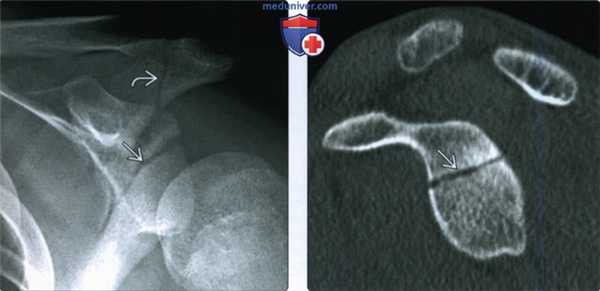

(Слева) На сагиттальной КТ с реформатированием у этого же пациента подтверждается перелом в основании клювовидного отростка, а также перелом акромиона (не показано). Переломы клювовидного отростка с минимальным смещением или наклоном обычно лечатся консервативно.

(Слева) На передне-задней рентгенограмме у пациента, жалующегося на боль в плечевом суставе через два дня после ДТП, видно просветление через поверхность суставной впадины, соответствующее перелому Идеберга II типа. Кроме того, имеется перелом акромиального отростка. Переломы были плохо видны на рентгенограмме грудной клетки.

(Справа) На сагиттальной КТ с реформатированием у этого же пациента подтверждается минимальное смещение поверхности суставной впадины. Переломы суставной впадины II типа с минимальным смещением обычно можно вылечить консервативно.